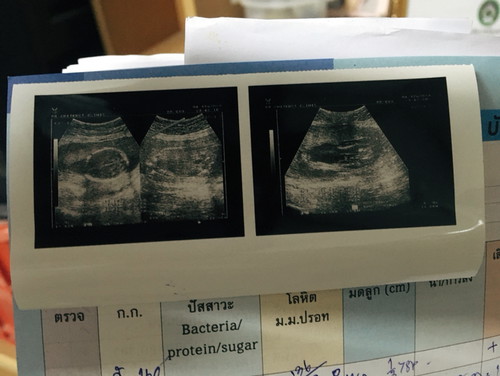

ในที่สุดก็สมใจแม่สักที คนแรกได้ผู้ชาย คนที่2ได้ลูกสาวจ้า ตอนนี้พร้อมปิดอู่มากๆ 19w แล้ว ตื่นเต้นไม่ต่างจากท้องแรกเลย กำหนดคลอด30เมษา 63 ปัจจุบันคนแรกเพิ่ง10เดือน20วันเอง แม่ยังนึกภาพความบันเทิงที่จะมาถึงเร็วๆนี้ไม่ออกเลยว่าจะเป็นยังไง หัวปีท้ายปีกันขนาดนี้??? มีคุณแม่ท่านไหนมีลูกต่อกันเร็วแบบนี้บ้างไหมคะ?? ??